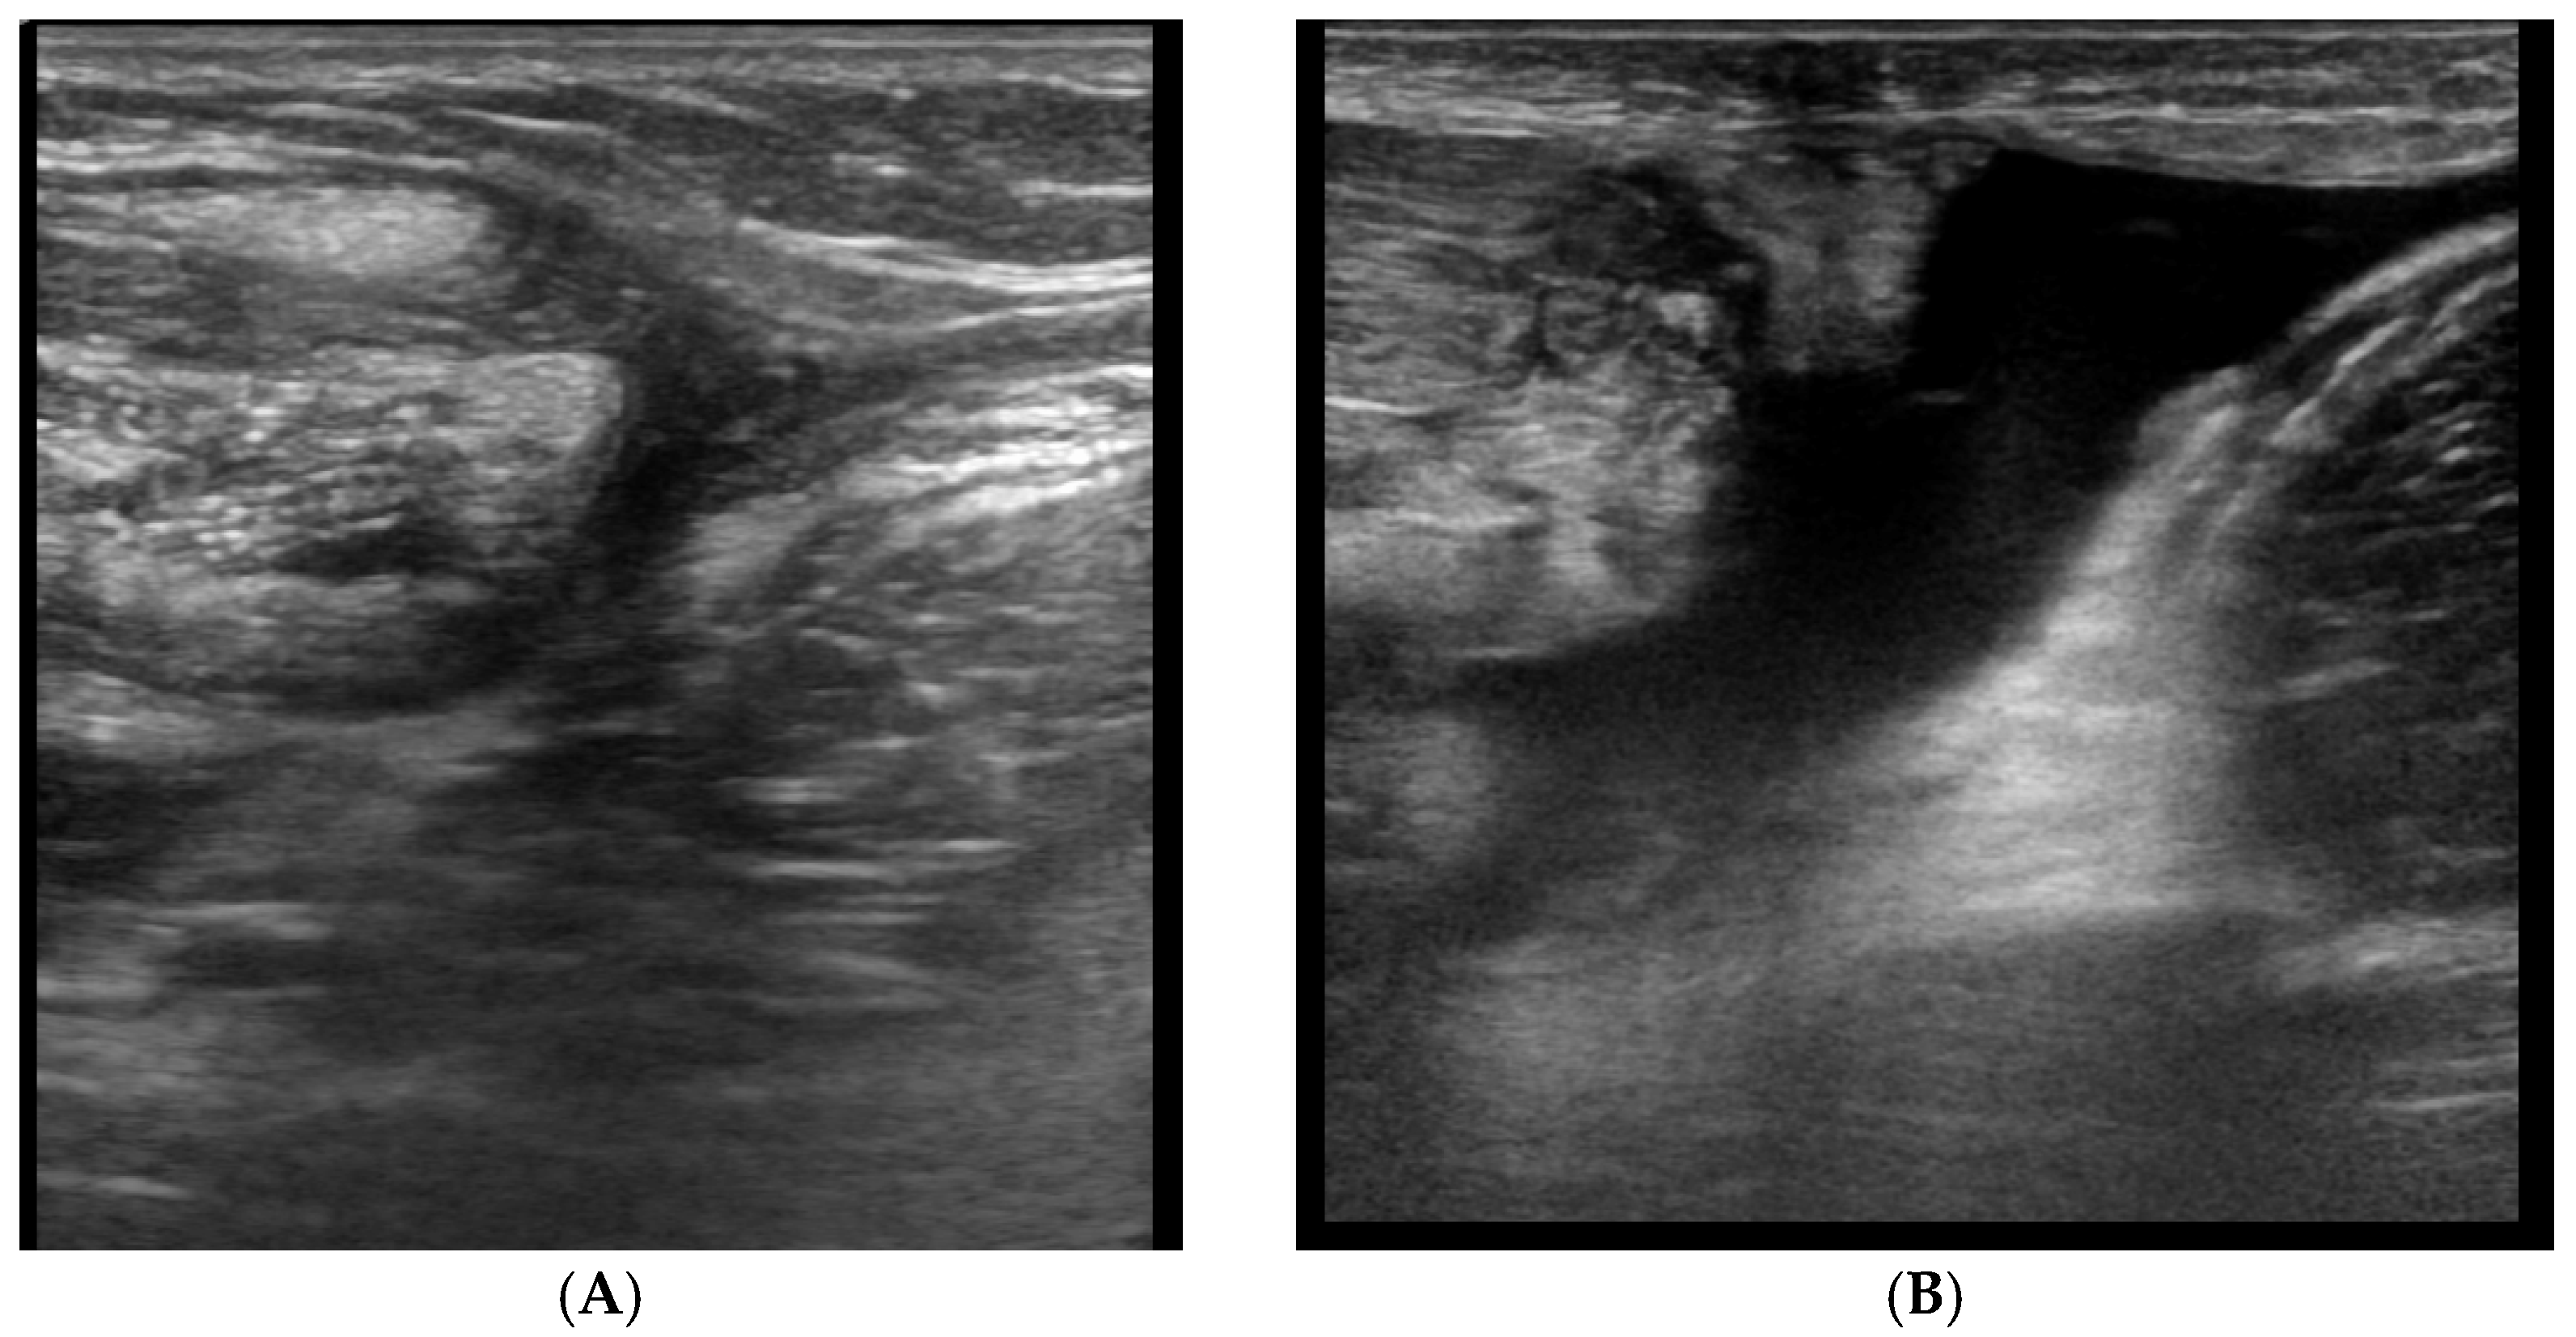

4.4. PM Tendon Tears